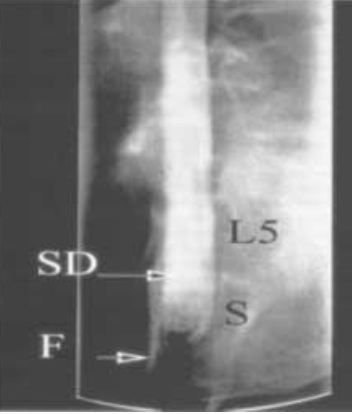

Figura nº 1. Cortesía del Dr. Royo-Salvador. Disección anatómica realizada en la Universidad de Barcelona, en donde se puede apreciar una sección sagital del sacro con el "filum terminale" (FT), la "cauda equina" (CE), los cuerpos vertebrales del sacro (S), de la 5ºvertebra lumbar (L5) y el fondo de saco dural (SD).

Las conclusiones del Dr. Royo así como los resultados de su nueva técnica quirúrgica sobre el "filum terminale" (FT) (Fig. nº 1), dan un nuevo impulso a la teoría de la existencia de una tensión medular que se extiende desde las inserciones de la duramadre en el interior del cráneo hasta el sacro mediante el "filum terminale".

Figuras nº 4. Cortesía del Dr. Royo-Salvador. Proyeccion frontales de un mielo-TAC del saco dural de la paciente de la figura nº 3. Se puede distinguir en el interior del saco dural relleno de contraste (en blanco) (SD) una imagen vertical y rígida (en negro) que corresponde a una FT a tensión. En la parte inferior está situado el sacro (S) y en la parte superior L5.

Figura nº 5. Cortesía del Dr. Royo-Salvador. Proyección lateral del mismo mielo-TAC de la figura nº 4. En la parte posterior del saco dural (SD), a nivel de S3, puede apreciarse una fuga del contraste (la imagen en blanco que señala la flecha) (F). Corresponde a una fístula en el saco dural por donde sale el líquido cefalorraquídeo. La presión del FT a tensión ha perforado la duramadre.